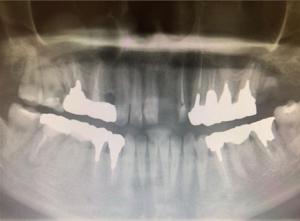

これが、そのエックス線画像。

白いところは人工物。金属です。薄い白いのが神経を取った後。

これは、よくある保険での治療です。

上下の奥歯・右も左もすべて銀歯。みーんな銀歯。つまり、この患者さんに与えられている噛み合わせは、元からではなく、担当した歯科医師が作ったものと。考えられる。